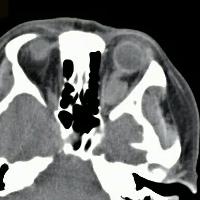

西 3037天前转移征象。 【体检辅查】 见上 【诊断】 泪腺癌